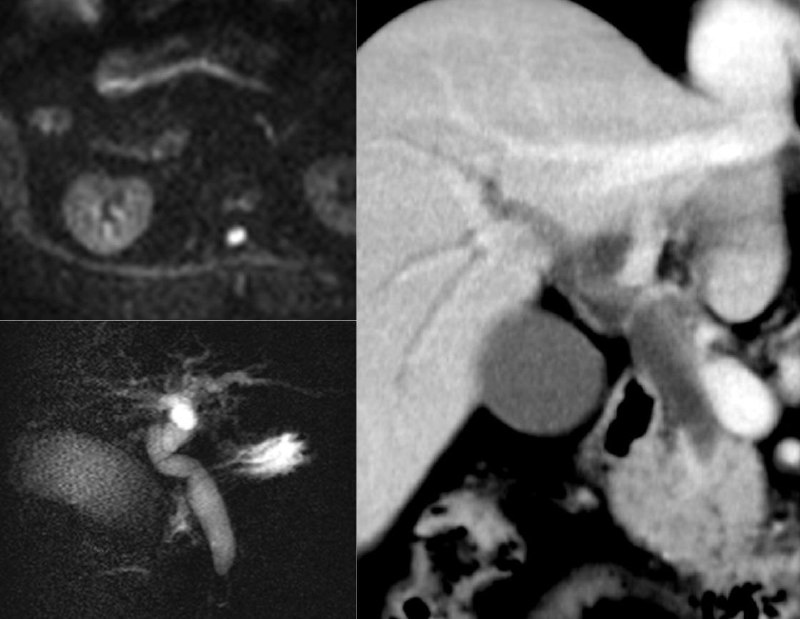

Редкая штука - дивертикул общего желчного протока. Формально - это киста 2 типа по Тодани, но не все исследователи согласны, что это - аномалия, а не приобретенное состояние.